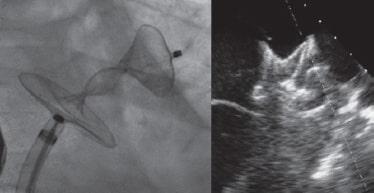

La intervención se llevó a cabo con un dispositivo Amulet de 28 mm. Se avanzó una vaina introductora de 14 Fr por vía transeptal a la aurícula izquierda y, tras una angiografía selectiva, se implantó el dispositivo dentro de la orejuela de forma habitual. Como el dispositivo no se colocó bien la primera vez (parcialmente fuera de la orejuela) hubo que recapturarlo. En el segundo intento y con una importante rotación de la vaina en sentido antihorario, el cuerpo del dispositivo quedó colocado con un peculiar «retorcimiento» (figura 2) con el extremo distal dentro de la orejuela. Se recapturó con cuidado y, tras descartar derrame pericárdico, se reimplantó, esta vez correctamente, sin ser necesario cambiar el dispositivo (figura 3). La ecocardiografía transtorácica realizada al día siguiente descartó la presencia de derrame pericárdico. La ETE que se realizó al cabo de 1 mes descartó la presencia de fugas o trombos en el dispositivo.

Figura 2.